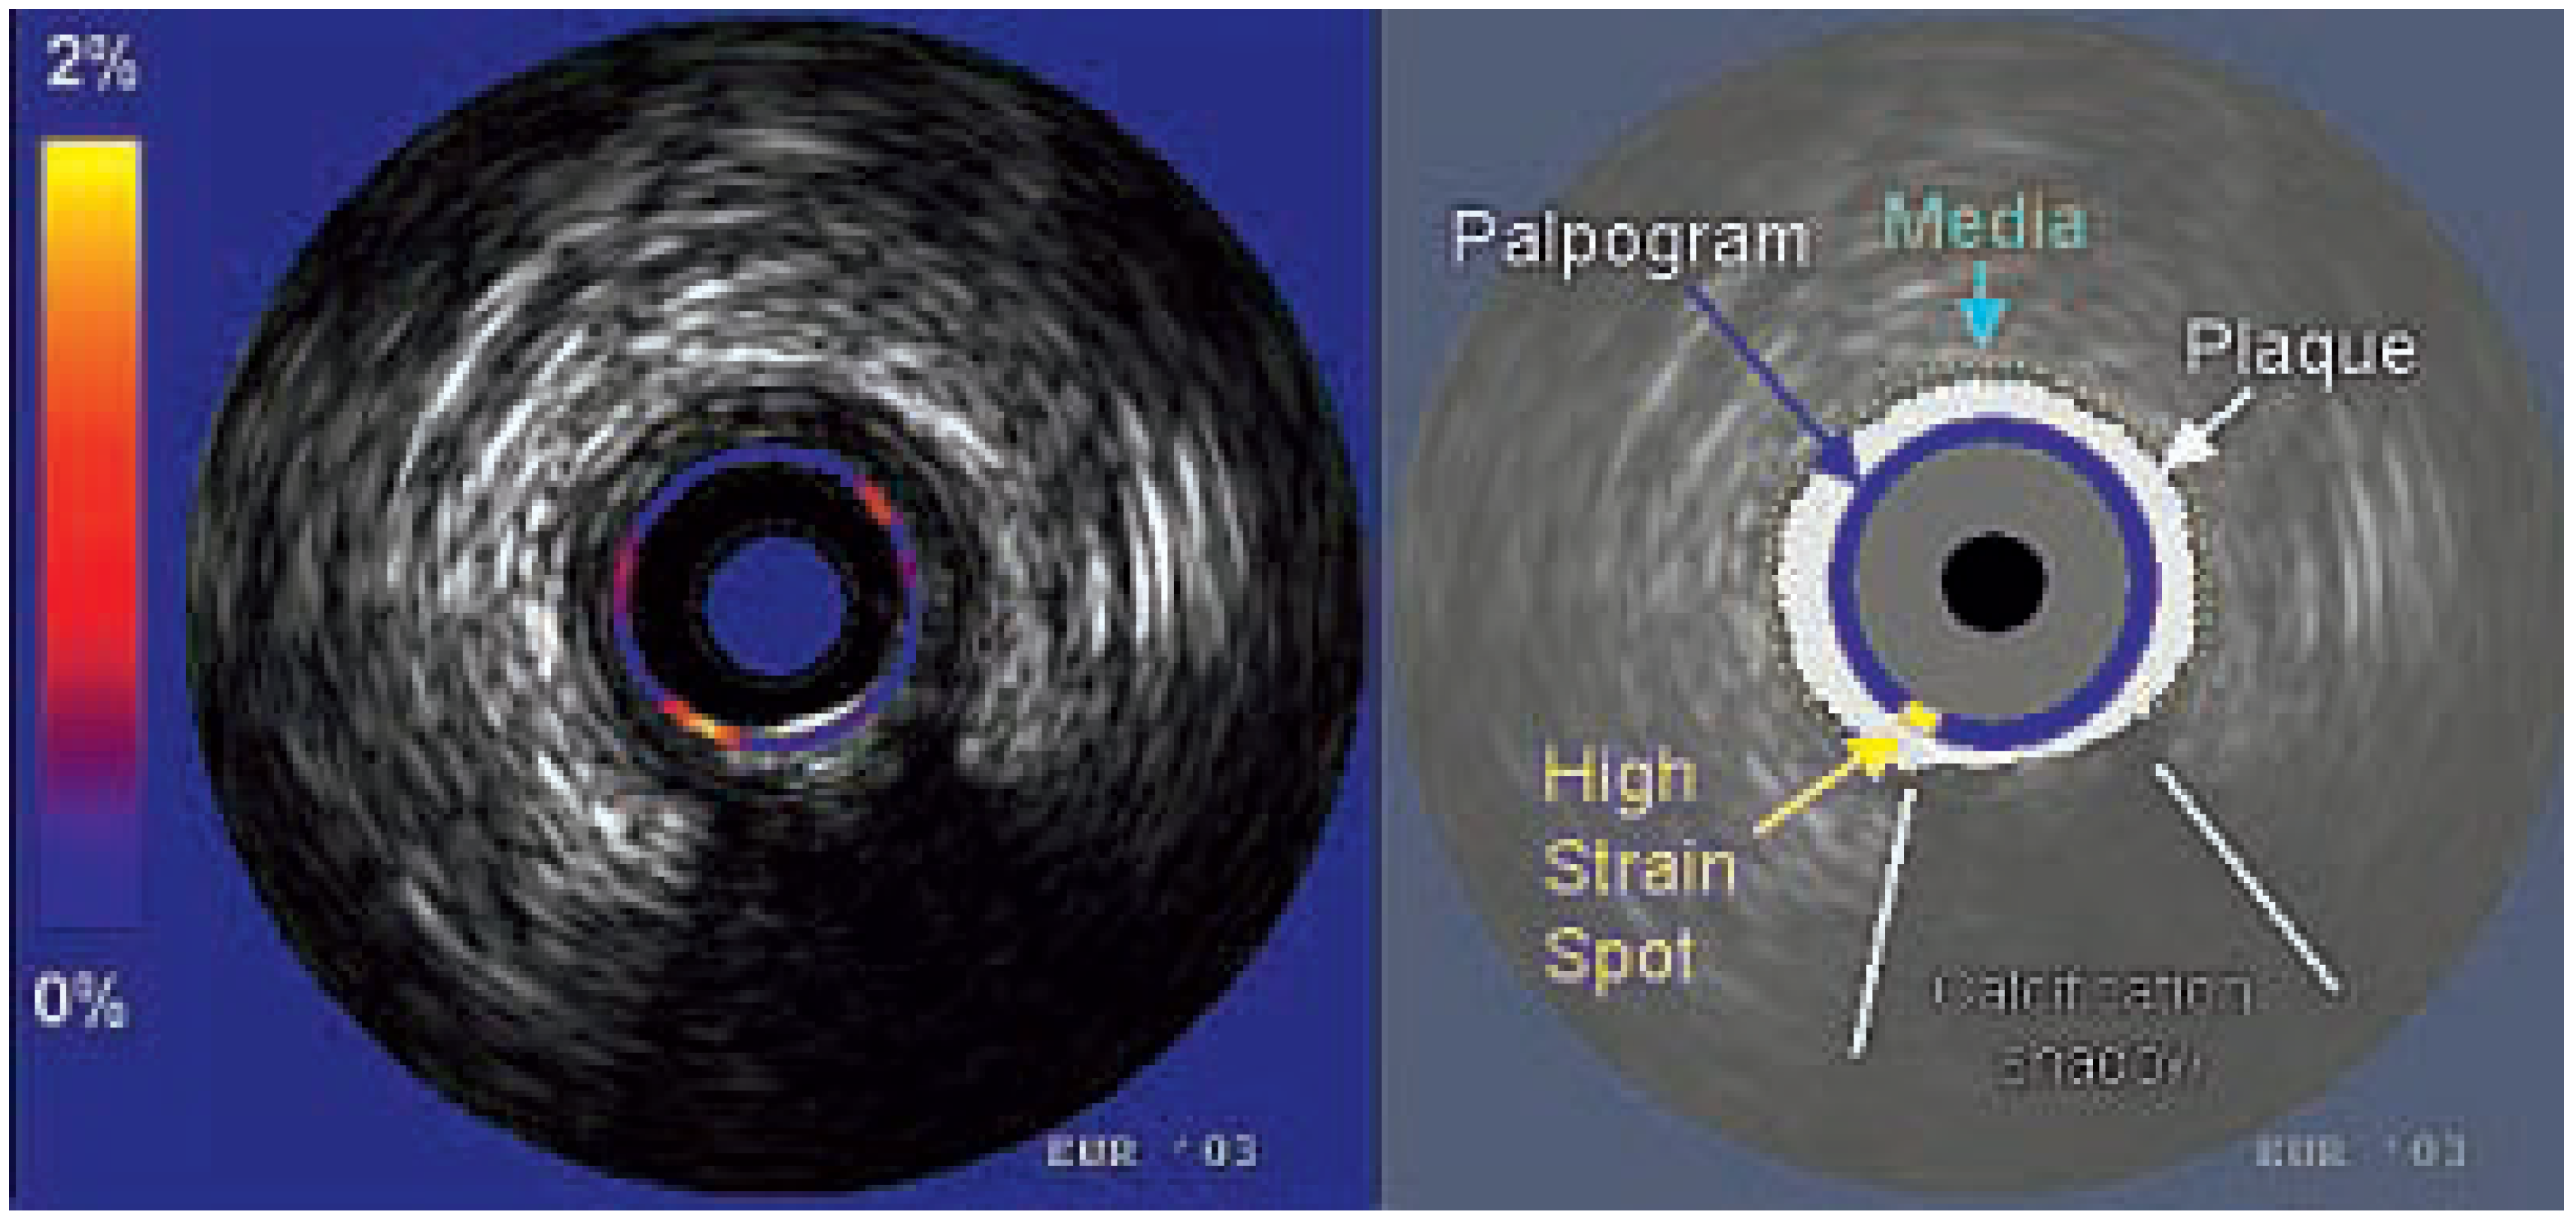

Intra-vascular elastography/palpography

- de Korte, C.L.; Pasterkamp, G.; van der Steen, A.F.; Woutman, H.A.; Bom, N. Characterization of plaque components with intravascular ultrasound elastography in human femoral and coronary arteries in vitro. Circulation 2000, 102, 617–623. [Google Scholar] [CrossRef] [PubMed]

- Schaar, J.A.; deKorte, C.L.; Mastik, F.; Strijder, C.; Pasterkamp, G.; Boersma, E.; et al. Characterizing vulnerable plaque features with intravascular elastography. Circulation 2003, 108, 2636–2641. [Google Scholar] [CrossRef] [PubMed]

- Doyley, M.M.; Mastik, F.; de Korte, C.L.; Carlier, S.C.; Cespedes, E.I.; Serruys, P.W.; et al. Advancing intravascular ultrasonic palpation toward clinical applications. Ultrasound Med Biol 2001, 27, 1471–1480. [Google Scholar] [CrossRef]

- Schaar, J.A.; Regar, E.; Mastk, F.; McFadden, E.P.; Saia, F.; Disco, C.; et al. Incidence of high strain patterns in human coronary arteries: assessment with three-dimensional intravascular palpography and correlation with clinical presentation. Circulation 2004, 109, 2716–2719. [Google Scholar] [CrossRef]